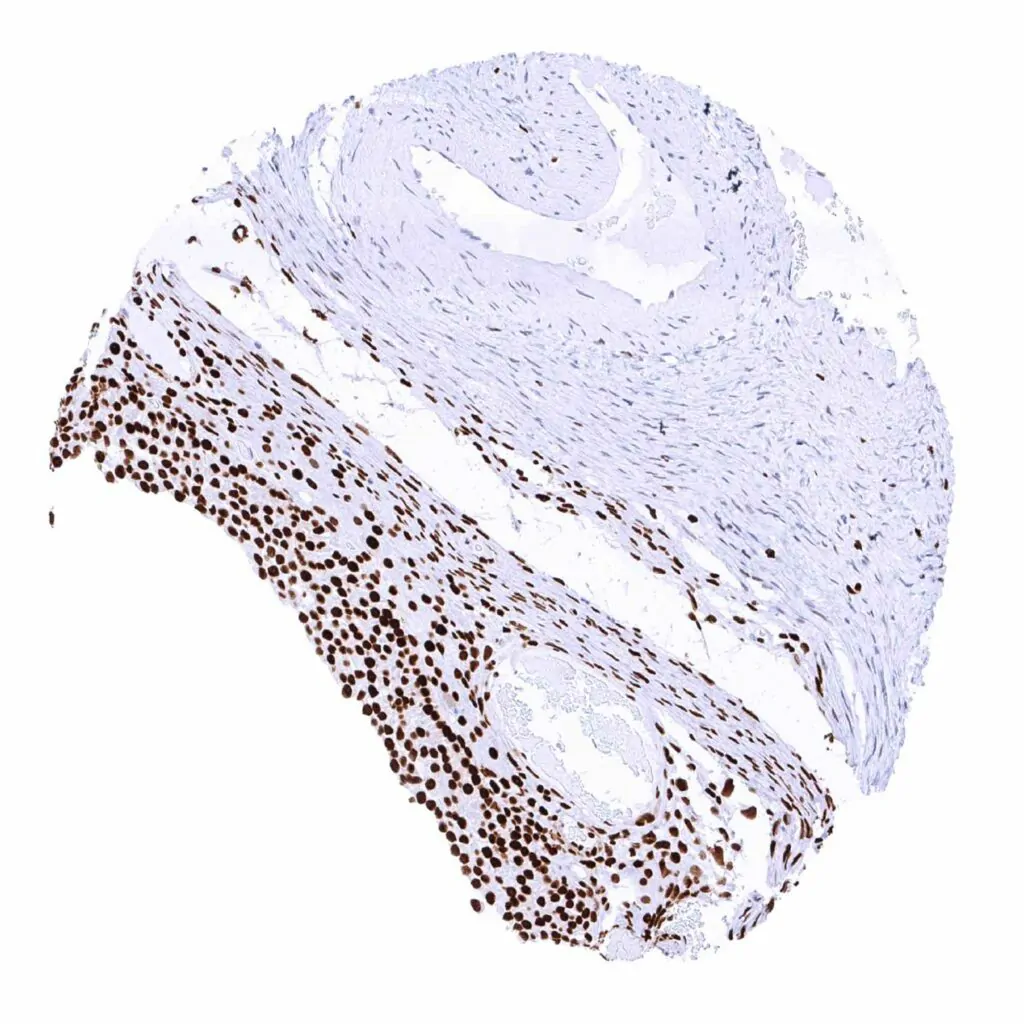

Esophagus, squamous epithelium – Esophageal squamous epithelium shows a moderate to strong MCM2 staining of suprabasal and basal cells

Uterus, ectocervix – The squamous epithelium shows a moderate MCM2 immunostaining of (mostly) suprabasal cells

Skin – Suprabasal and basal cell layers (weaker) of the squamous epithelium show a distinct MCM2 positivity

Tonsil – A large fraction of lymphocytes is at least weakly MCM2 positive. In the tonsil crypts, many epithelial cells (basal-suprabasal) are MCM2 positive